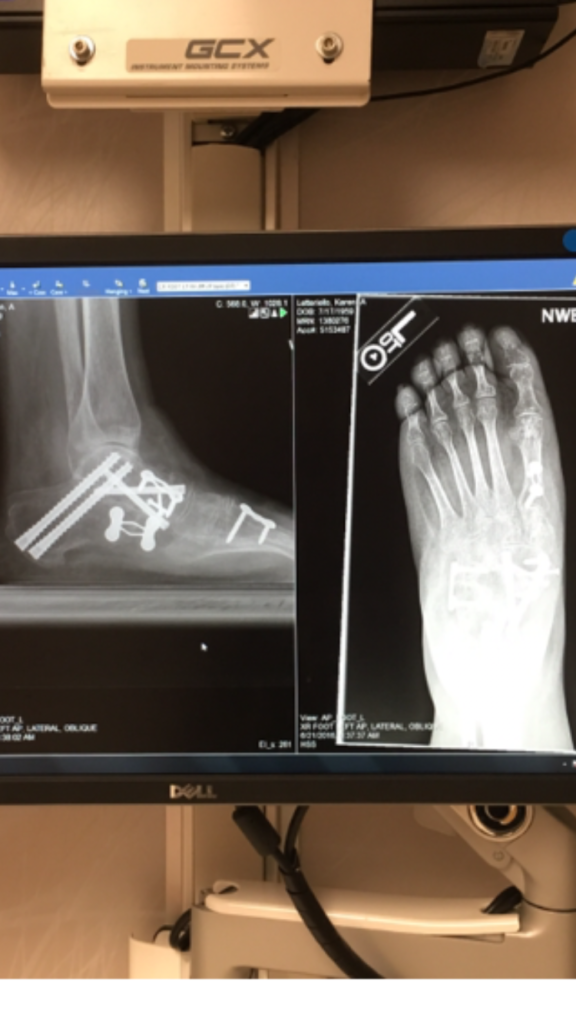

Walking in pain became my life. After countless doctors I tried HSS. Dr Demetracopoulos. I still remember those four words..."I can fix this." I cried. March 30th was my five hour surgery. My foot was fused on the top and the outside. I have 13 pins and 3 plates. He also repaired my Achilles. Recovery has been long. Dr. Demetracopoulos told me it would be six months before I would walk. Now at 23 weeks post-op I have no walker, no cane! When I first took a few steps I was amazed. My new favorite four words are "Dr. D fixed it." The entire staff at HSS from the door greeters, X-Ray, Losant and Vanessa have been so caring. Dr. Demetracopoulos is an incredibly skilled surgeon. He is a miracle worker. I have a life back thanks to him. Don't put it off. Get your life back too.